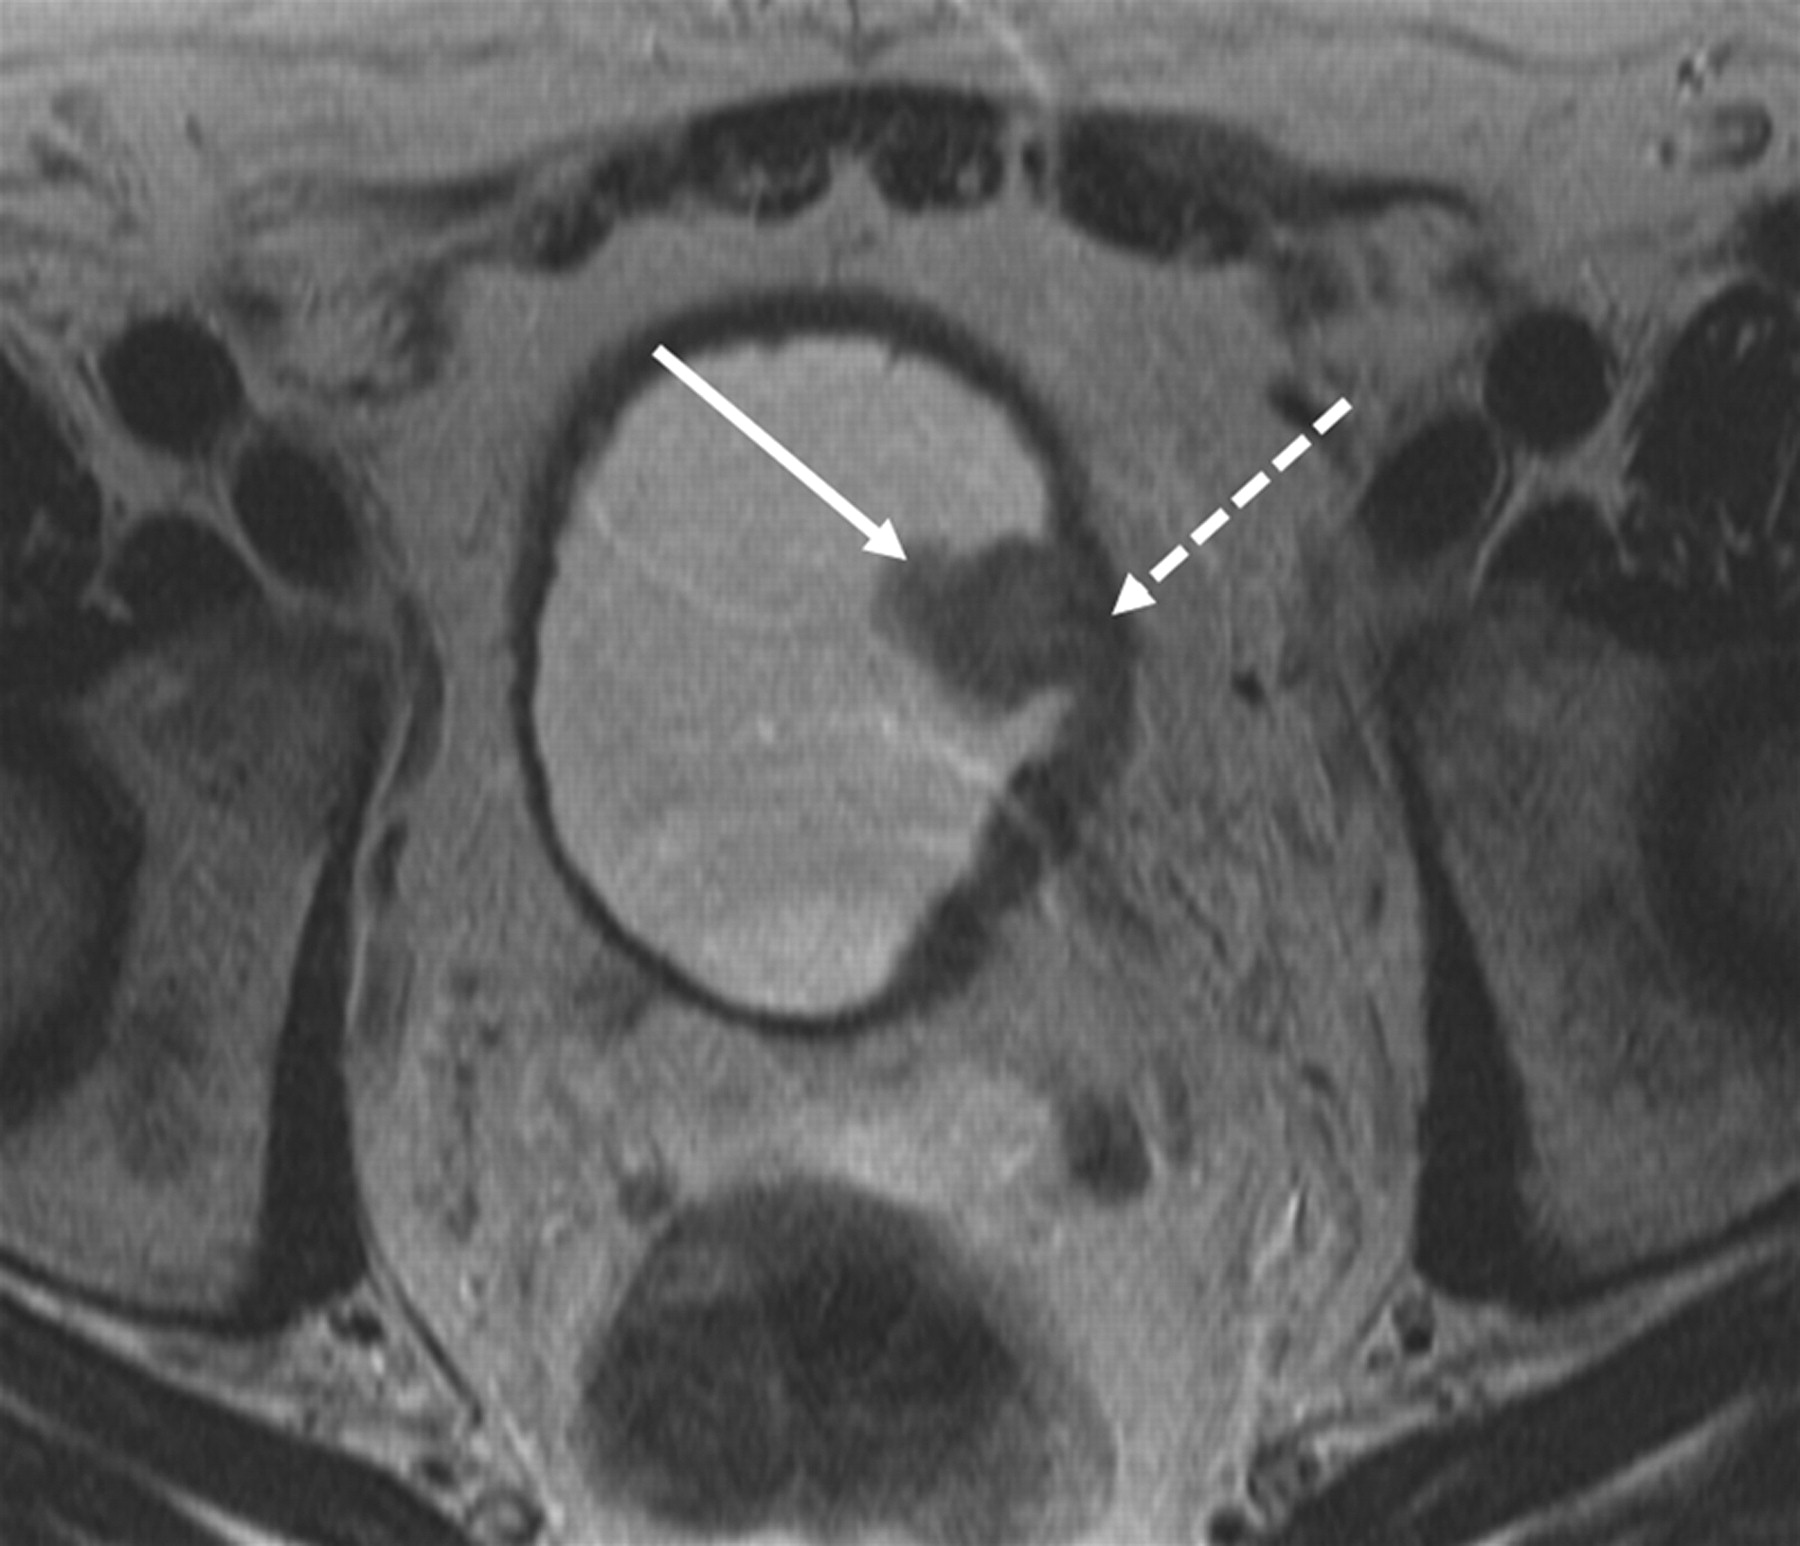

Изображения КТ конкрементов мочевого пузыря